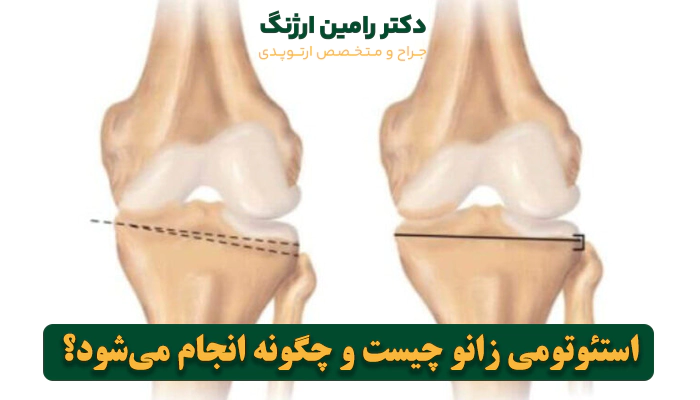

استئوتومی زانو (Knee Osteotomy) یکی از تکنیکهای جدید در علم روز ارتوپدی است که برخلاف تعویض مفصل، هدف اصلی آن این است که مفصل اصلی زانو را حفظ کند. واژه “استئو” به معنای استخوان و “تومی” به معنای برش است؛ بنابراین، استئوتومی در واقع به معنای “بریدن استخوان” است.

در این جراحی، جراح یک برش کوچک و کنترل شده روی یکی از استخوانهای اطراف مفصل زانو (معمولاً استخوان درشتنی یا تیبیا در زیر زانو و گاهی استخوان ران یا فمور در بالای زانو) ایجاد میکند. سپس، برای اینکه محور کلی پا را اصلاح و طبیعی کند، مقداری از استخوان را حذف یا مقداری اضافه میکند.